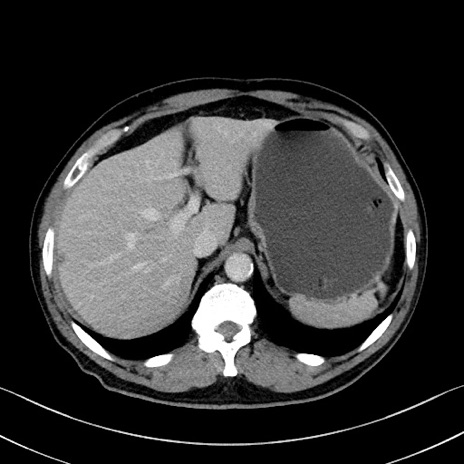

症例35(横断像)

【症例】70歳代 男性

【主訴】腹部膨満、嘔吐

【現病歴】昨日より腹部膨満感出現。本日増悪し、仙痛出現。嘔吐あり、受診。

【既往歴】糖尿病、胆摘後

【身体所見】BP 149/80mmHg、HR 74/min、BT 35.9℃、腹部:膨満、軟、圧痛なし。腸雑音減弱あり。上腹部正中切開瘢痕あり。

【データ】WBC 13500、CRP 1.72